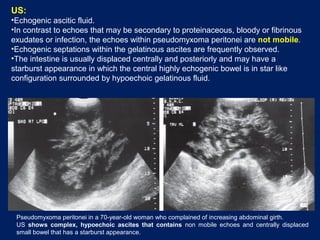

US:

•Echogenic ascitic fluid.

•In contrast to echoes that may be secondary to proteinaceous, bloody or fibrinous

exudates or infection, the echoes within pseudomyxoma peritonei are not mobile.

•Echogenic septations within the gelatinous ascites are frequently observed.

•The intestine is usually displaced centrally and posteriorly and may have a

starburst appearance in which the central highly echogenic bowel is in star like

configuration surrounded by hypoechoic gelatinous fluid.

Pseudomyxoma peritonei in a 70-year-old woman who complained of increasing abdominal girth.

US shows complex, hypoechoic ascites that contains non mobile echoes and centrally displaced

small bowel that has a starburst appearance.